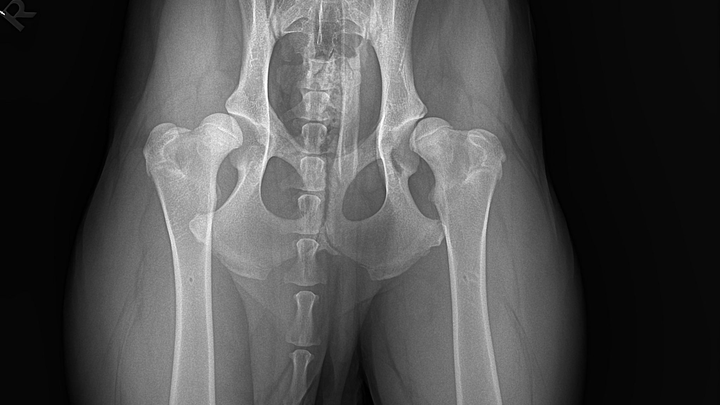

Leider musste ich früh feststellen, dass mit diesem kleinen Würmchen etwas nicht stimmt. Also mache ich einen Termin in der Tierklinik. Nach einem Röntgen seiner Hüfte wurde mein schlechtes Gefühl und schlimme Befürchtung bestätigt: Die Tierärzte haben mir mitgeteilt, dass seine Situation ernst ist und beide Seiten seiner Hüfte betroffen sind. Diese Nachricht hat mein Herz gebrochen.